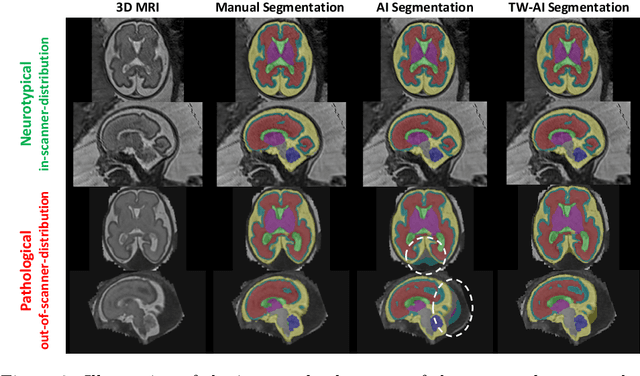

Abstract:Deep learning models for medical image segmentation can fail unexpectedly and spectacularly for pathological cases and for images acquired at different centers than those used for training, with labeling errors that violate expert knowledge about the anatomy and the intensity distribution of the regions to be segmented. Such errors undermine the trustworthiness of deep learning models developed for medical image segmentation. Mechanisms with a fallback method for detecting and correcting such failures are essential for safely translating this technology into clinics and are likely to be a requirement of future regulations on artificial intelligence (AI). Here, we propose a principled trustworthy AI theoretical framework and a practical system that can augment any backbone AI system using a fallback method and a fail-safe mechanism based on Dempster-Shafer theory. Our approach relies on an actionable definition of trustworthy AI. Our method automatically discards the voxel-level labeling predicted by the backbone AI that are likely to violate expert knowledge and relies on a fallback atlas-based segmentation method for those voxels. We demonstrate the effectiveness of the proposed trustworthy AI approach on the largest reported annotated dataset of fetal T2w MRI consisting of 540 manually annotated fetal brain 3D MRIs with neurotypical or abnormal brain development and acquired from 13 sources of data across 6 countries. We show that our trustworthy AI method improves the robustness of a state-of-the-art backbone AI for fetal brain MRI segmentation on MRIs acquired across various centers and for fetuses with various brain abnormalities.